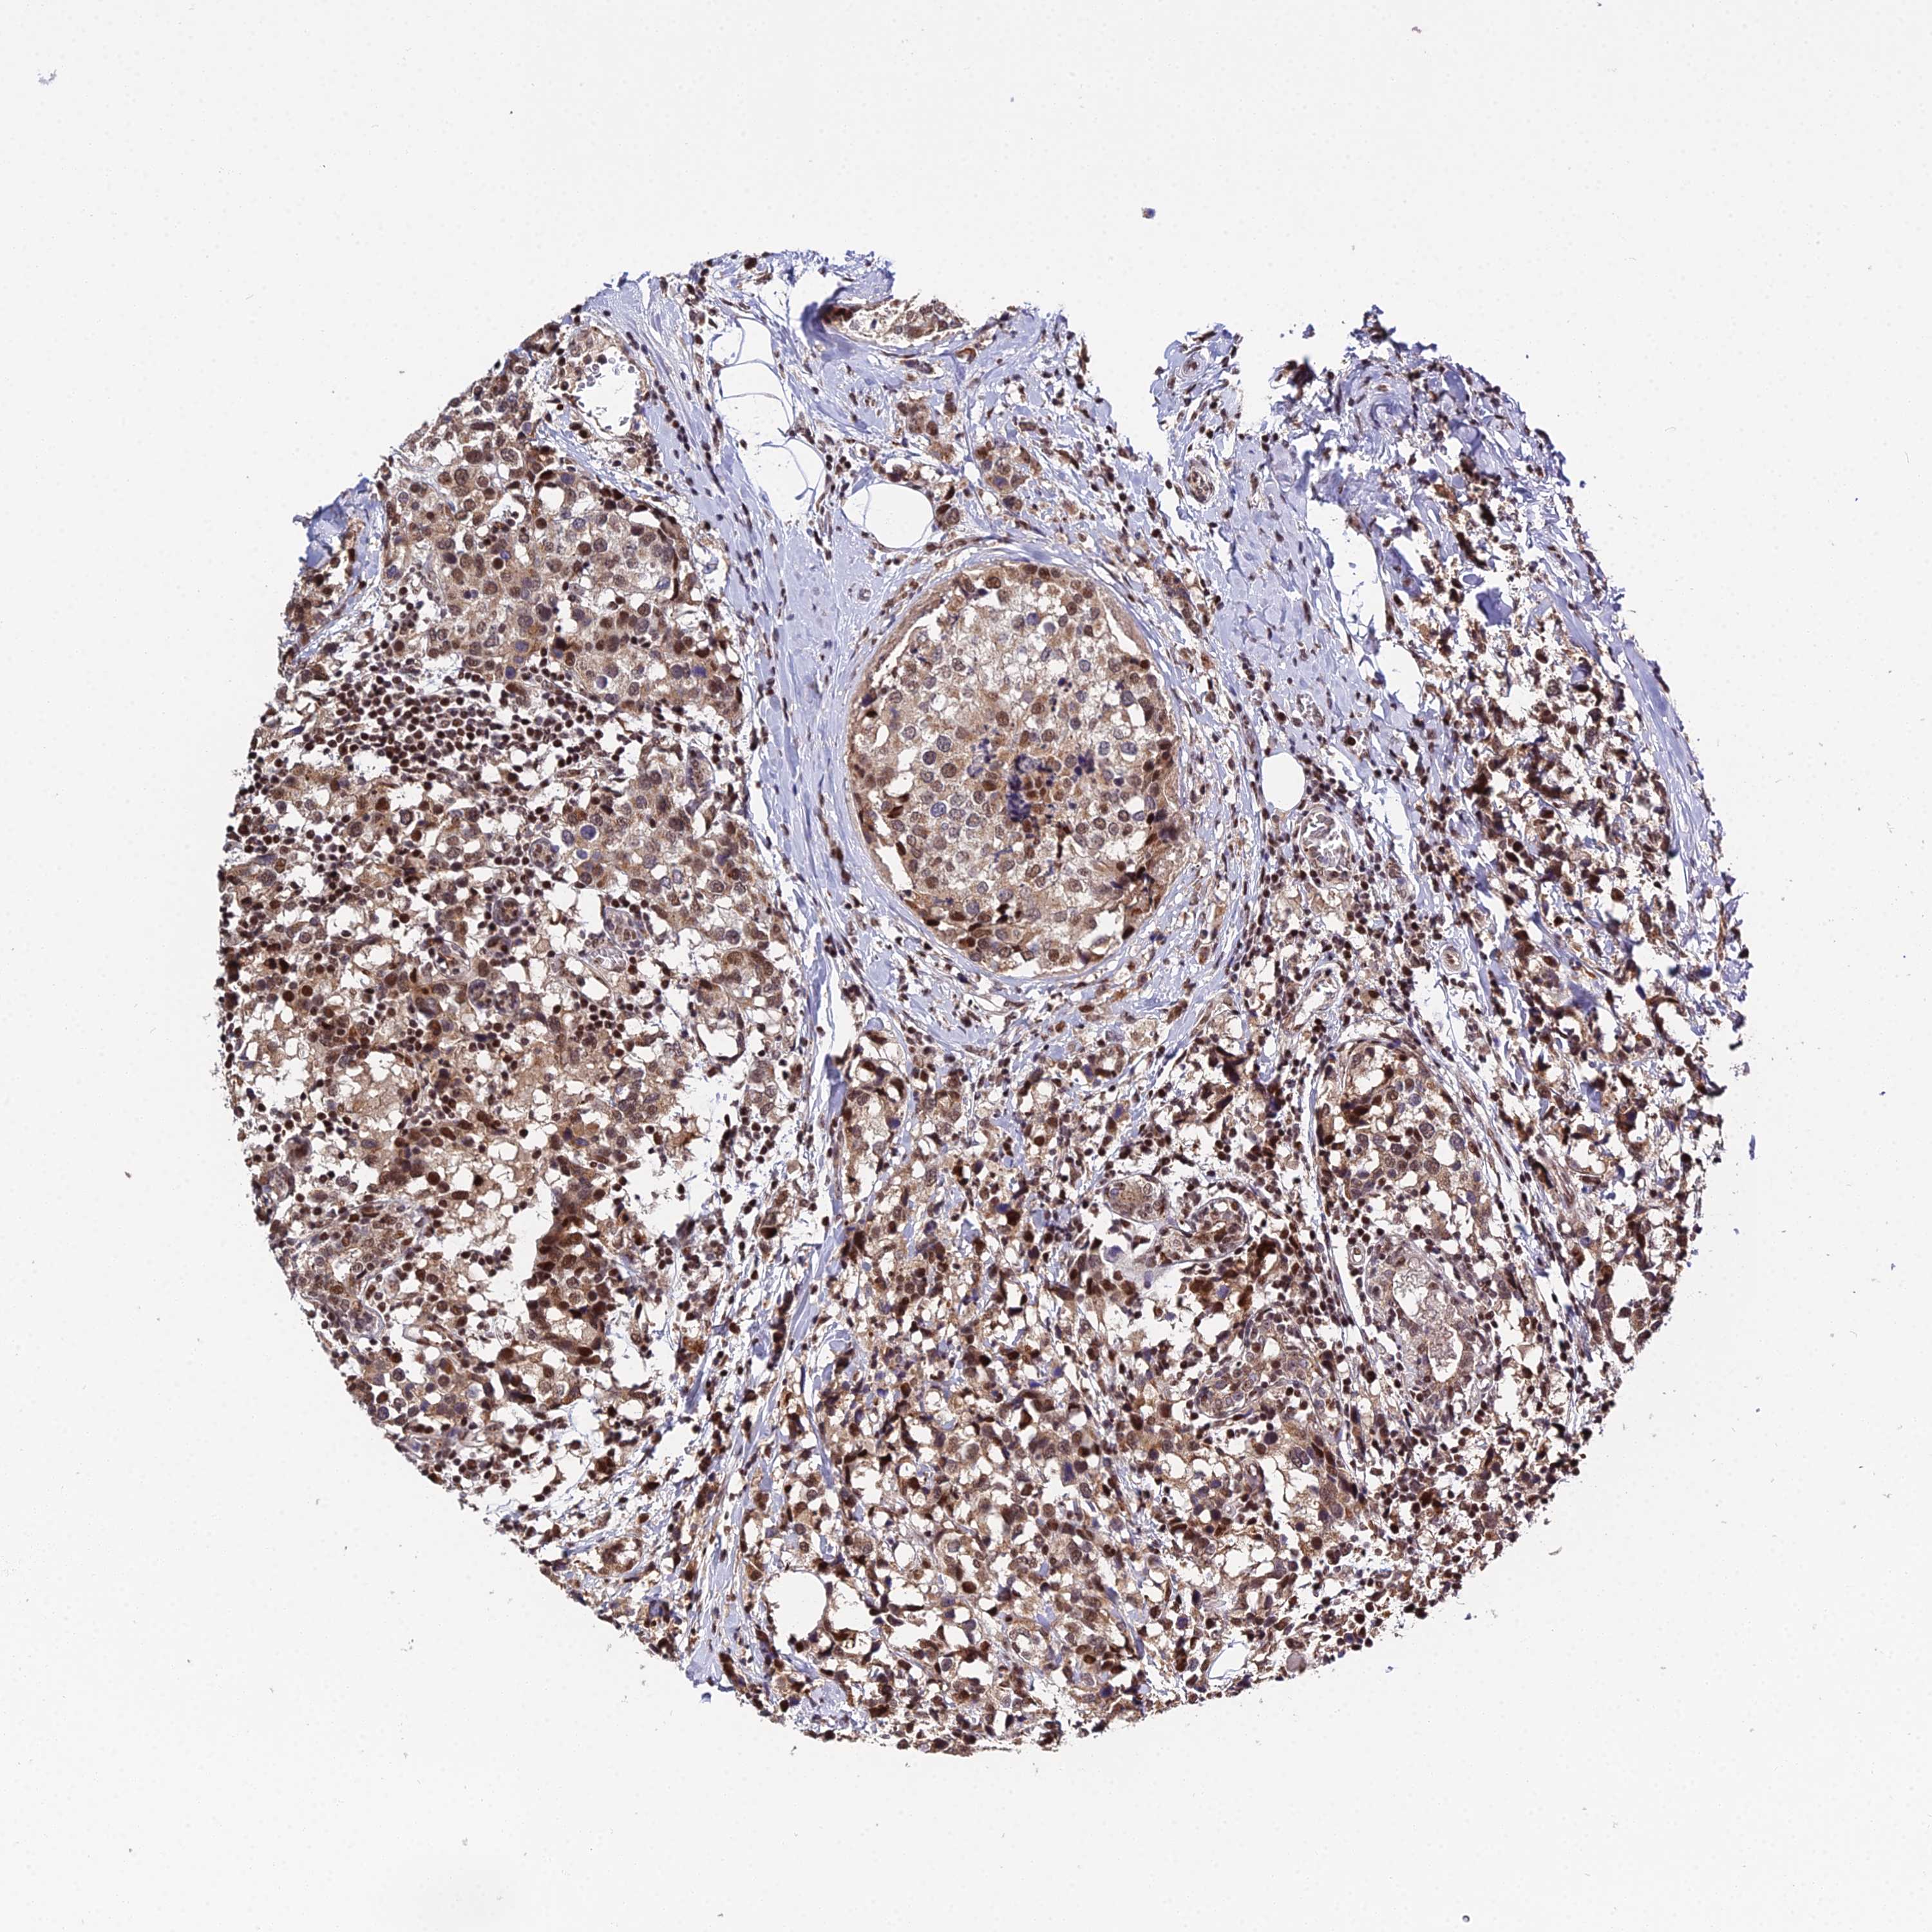

Breast cancer

Human cancer

Breast invasive carcinoma